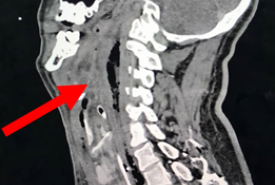

Retropharyngeal Abscess with a Missed Migrating Foreign Body: A Case Report

Case Report 29 Jan, 2026